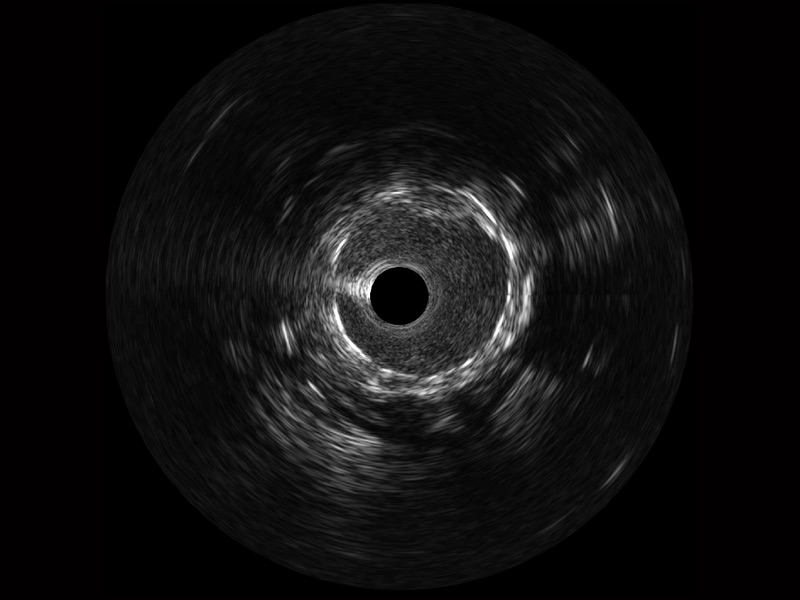

• 16877太阳集团宽频IVUS图像

• 传统IVUS图像

对比传统IVUS导管成像,16877太阳集团宽频IVUS图像的近场支架梁显影更细腻,远场中膜外血管仍清晰可辨,兼顾远中近,兼顾分辨力与穿透深度

临床图

远场分支血管及导丝

支架内血栓

组织脱垂